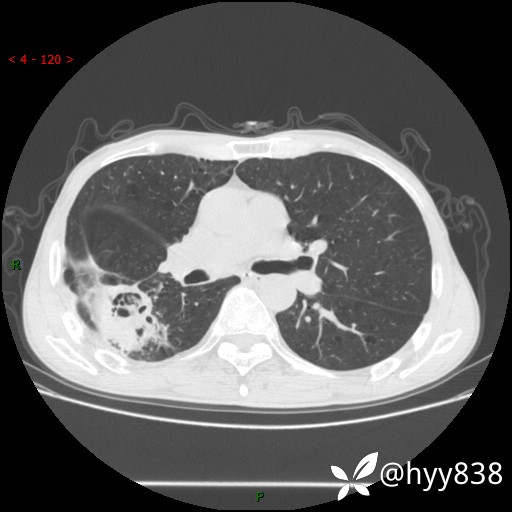

老年男性,肺团片状占位+体重下降,肿瘤 VS 真菌 VS 细菌,看看你的意见--结果公布~

简要病史:患者7天前无明显诱因出现咳嗽咳痰,咳绿色、褐色痰,吸烟后加重,伴心慌、胸闷,无畏寒发热,无头晕头痛,无鼻塞流涕,无痰中带血及咯血,无胸痛、呼吸困难,无全身酸痛,为求进一步诊治于我院就诊,门诊完善胸部CT提示“右下肺团片状影,考虑肿瘤?感染?”,门诊以“咳嗽待查”收住入院。 起病以来,患者精神、饮食、睡眠尚可,大、小便正常,体力下降,体重下降8斤。空腹血糖:6.42mmol/L。

辅助检查:CT

临床诊断:肿瘤?感染?

胸部CT平扫

增强动脉期

静脉期